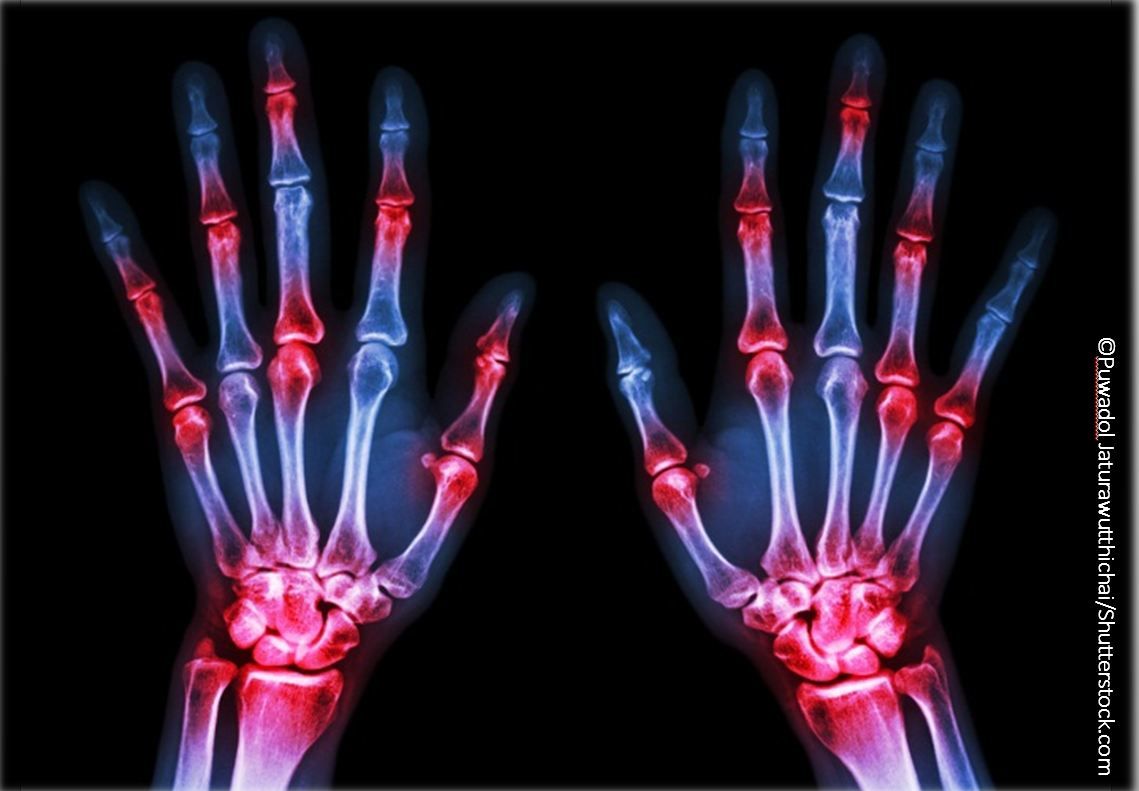

RA can be managed in primary care but comes with unique challenges. Here, strategies outlined at the ACP Internal Medicine Meeting 2018.

With so many treatment choices available, the potential for successfully treating joint disease in rheumatoid arthritis (RA) is very high – as is the potential for treatment side effects, said David A. Fox, MD, Chief of the Division of Rheumatology at the University of Michigan, Ann Arbor.

Add in the potential for disease-related complications, and the management of RA remains a major challenge for internists, who presented an update on RA treatments and complications at the ACP Annual Meeting 2018 in New Orleans, Louisiana.